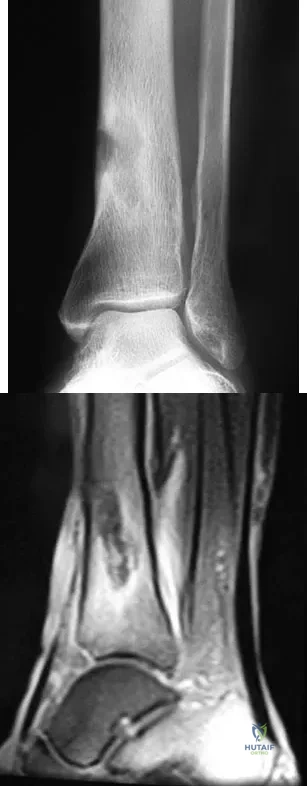

A 19-year-old girl has had pain and swelling in the right ankle for the past 4 months. She denies any history of trauma. Examination reveals a small soft-tissue mass over the anterior aspect of the ankle and slight pain with range of motion of the ankle joint. The examination is otherwise unremarkable. A radiograph and MRI scan are shown in Figures 45a and 45b, and biopsy specimens are shown in Figures 45c and 45d. What is the most likely diagnosis?

A 51-year-old man sustained an open fracture of his tibia in Korea 42 years ago. An infection developed and it was resolved with surgical treatment. For the past 6 months, an ulcer with mild drainage has developed over the medial tibia. The ulcer is small and there is minimal erythema at the ulcer site. A radiograph and MRI scan are shown in Figures 43a and Figure 43b. Initial cultures show Staphylococcus aureus susceptible to the most appropriate antibiotics. Laboratory studies show an erythrocyte sedimentation rate of 70 mm/h. What is the most appropriate surgical treatment at this time?